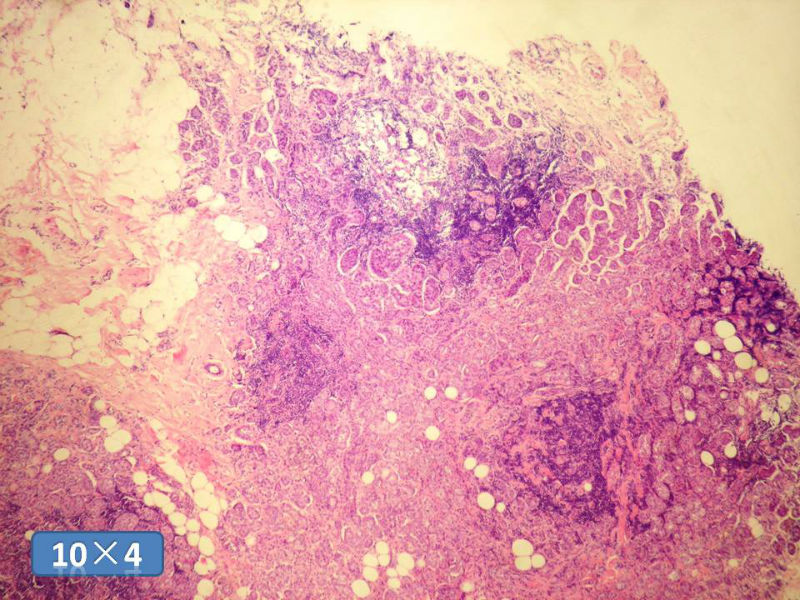

女性,50岁,乳腺肿物,冰冻切片(图1-25)

HE